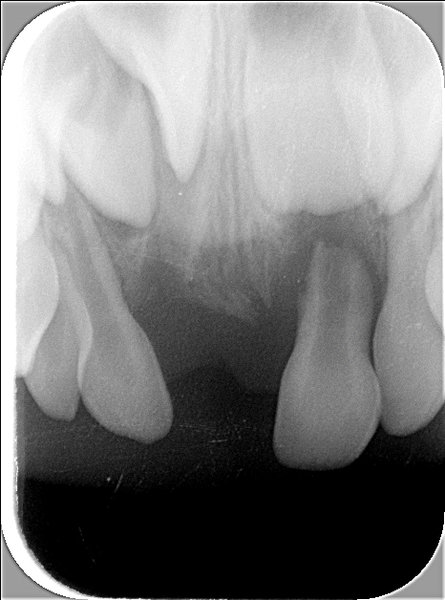

- Vorzeitiger Verlust von zwei oberen mittleren Milch-Schneidezähnen infolge eines Sturzes (der rechte, 51, wurde direkt nach dem Sturz entfernt, der linke, 61, musste etwa 6 Monate danach entfernt werden, da sich im Knochen an der Wurzel eine Entzündung gebildet hatte). Beide Zähne sind auf dem klinischen Bild schon nicht mehr zu sehen. Die Entzündung im Knochen und die vorzeitige Auflösung der Wurzel des Zahnes 61 sind auf dem Röntgenbild 1 mit schwarzen Pfeilen markiert.

Röntgenbild 1

Dieses zeigt das Standard-Oberkiefer-Front-Röntgenbild, das gemacht wurde, um die Entzündung des linken mittleren Schneidezahnes darzustellen (schwarze Pfeile). Ebenfalls ist darauf zusehen, dass der Zahn 11 (mittlerer bleibender Schneidezahn) noch etwas «verdreht» im Knochen steht, sowie der vermutete überzählige Zahn 12'.